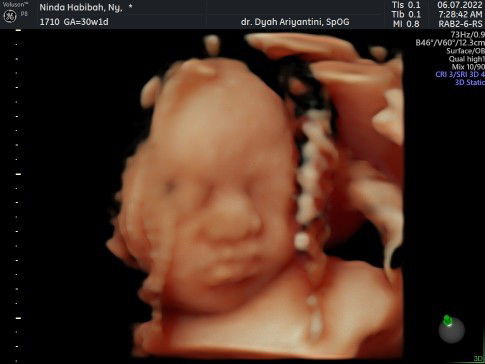

Alhamdulillah dedek utun kepala sudah dibawah bun, berat badan 1500gram, usia kehamilan 30 minggu, semoga menetap dan bisa masuk panggul diwaktu yang tepat.. sehat selalu. MasyaAllah Tabarokallah Yang hpl September semangat yah... Jaga kesehatan jiwa dan raga buat persiapan lahiran nanti 🥰 #bantusharing #shareaja